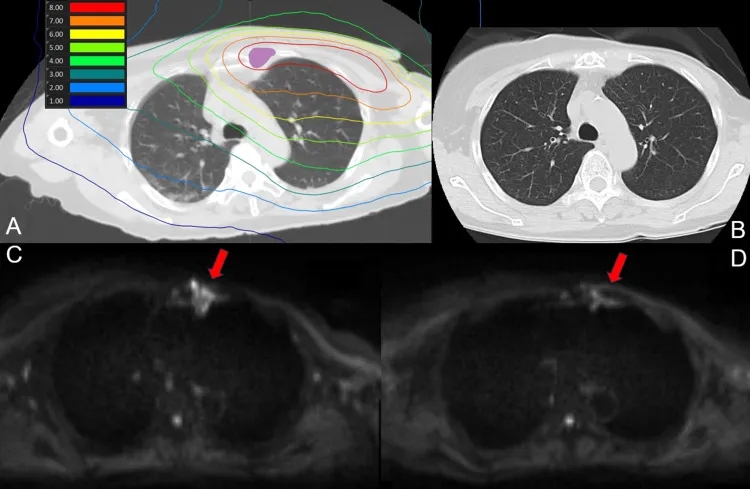

结果显示:BNCT后1天、7天MRI检查及30天、90天CT扫描,均未显示放射性肺炎迹象。下图1为肺部剂量分布及治疗后90天CT、MRI扫描。

▲图源“Cureus”,版权归原作者所有,如无意中侵犯了知识产权,请联系我们删除

①图1 A:BNCT(肺部)剂量分布图。紫色代表 GTV。

②图1 B:治疗后90天的CT扫描未显示放射性肺炎的迹象。

③图1 C:治疗前弥散加权成像MRI。

④图1 D:治疗90天的MRI扫描显示,信号强度下降。